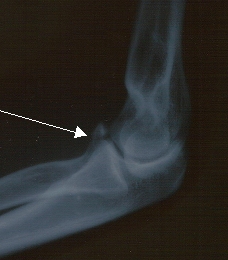

下腕内側の出っ張り。下腕が一旦外側に脱臼してここが折れたということらしい。

8月7日、青梅の山里走行中突然前方を横断し始めた爺さんを急減速・斜行で避けた仲間と接触・転倒、左肘骨折。9日からCOILの関西東海ツアーだっていうのに。思えば2001年9月飛び出してきた子供の自転車をよけてガードレールに突っ込み鎖骨骨折、この時はツアー4日前、今回はツアー2日前の骨折、なんと同じバンドである。鬼怒が代役にナスノミツル君の手配もしたのだがここで欠場したのでは「もう自転車はやめてくれ」と言われかねない。日本自転車界の為にも無謀とも言える決断をしてカルシウムとコラーゲンの錠剤をむさぼりつつ名古屋・京都・神戸・豊橋と直角ギブス姿で弾きまくった。こんなことをしてて骨はちゃんと付くのだろうか。幸いにしてCOIL後は戻り日(土曜)と日曜の休みを挟んで麗蘭リハが1日、あとはKIKI Band のミックス2日、SALT 再発2枚組のマスタリング1日という具合で金曜の北海道ライジングサンRock Fes までライブはない。育ってくれ、我が骨よ。毎回医者に回復が早くて感心されるが今回はいかに。